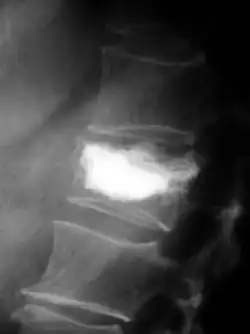

Les fractures pathologiques sont des fractures de l’os qui surviennent sans atteinte extérieure, à cause d'un affaiblissement pathologique de la matrice osseuse. Les métastases surtout ostéolytiques, mais aussi parfois ostéocondensantes, affaiblissent l’os concerné qui selon les circonstances peut être sursollicité par des contraintes mécaniques faibles, et rompt. Ces fractures peuvent survenir dans des situations de tous les jours, comme le fait de se lever d'un siège ou de déplacer le patient[77]. Pour les métastases ostéocondensantes, l'épaisseur de l’os est certes augmentée, mais sa solidité est abaissée par sa construction complètement non structurée[6]. Dans le domaine de la colonne vertébrale, elles peuvent conduire à des enraidissements[65].

Ce sont la plupart du temps les côtes ou les corps vertébraux qui sont atteints par les fractures. Les fractures dans les os longs, en particulier au col du fémur, présentent une gravité particulièrement élevée et sont le principal motif pour une intervention chirurgicale. Les fractures des corps vertébraux peuvent conduire à des syndromes de compression médullaire[65].

Les fractures de compression d'un ou plusieurs corps vertébraux peuvent conduire à une compression médullaire ou à un syndrome de la queue de cheval et sont des complications redoutées d'une métastase osseuse dans une vertèbre[80]. Les syndromes de compression médullaire se traduisent la plupart du temps par de fortes douleurs dorsales, ainsi que des insuffisances motrices et sensitives des extrémités inférieures. Le contrôle de la vessie et du rectum peuvent aussi être détériorés par la compression médullaire.